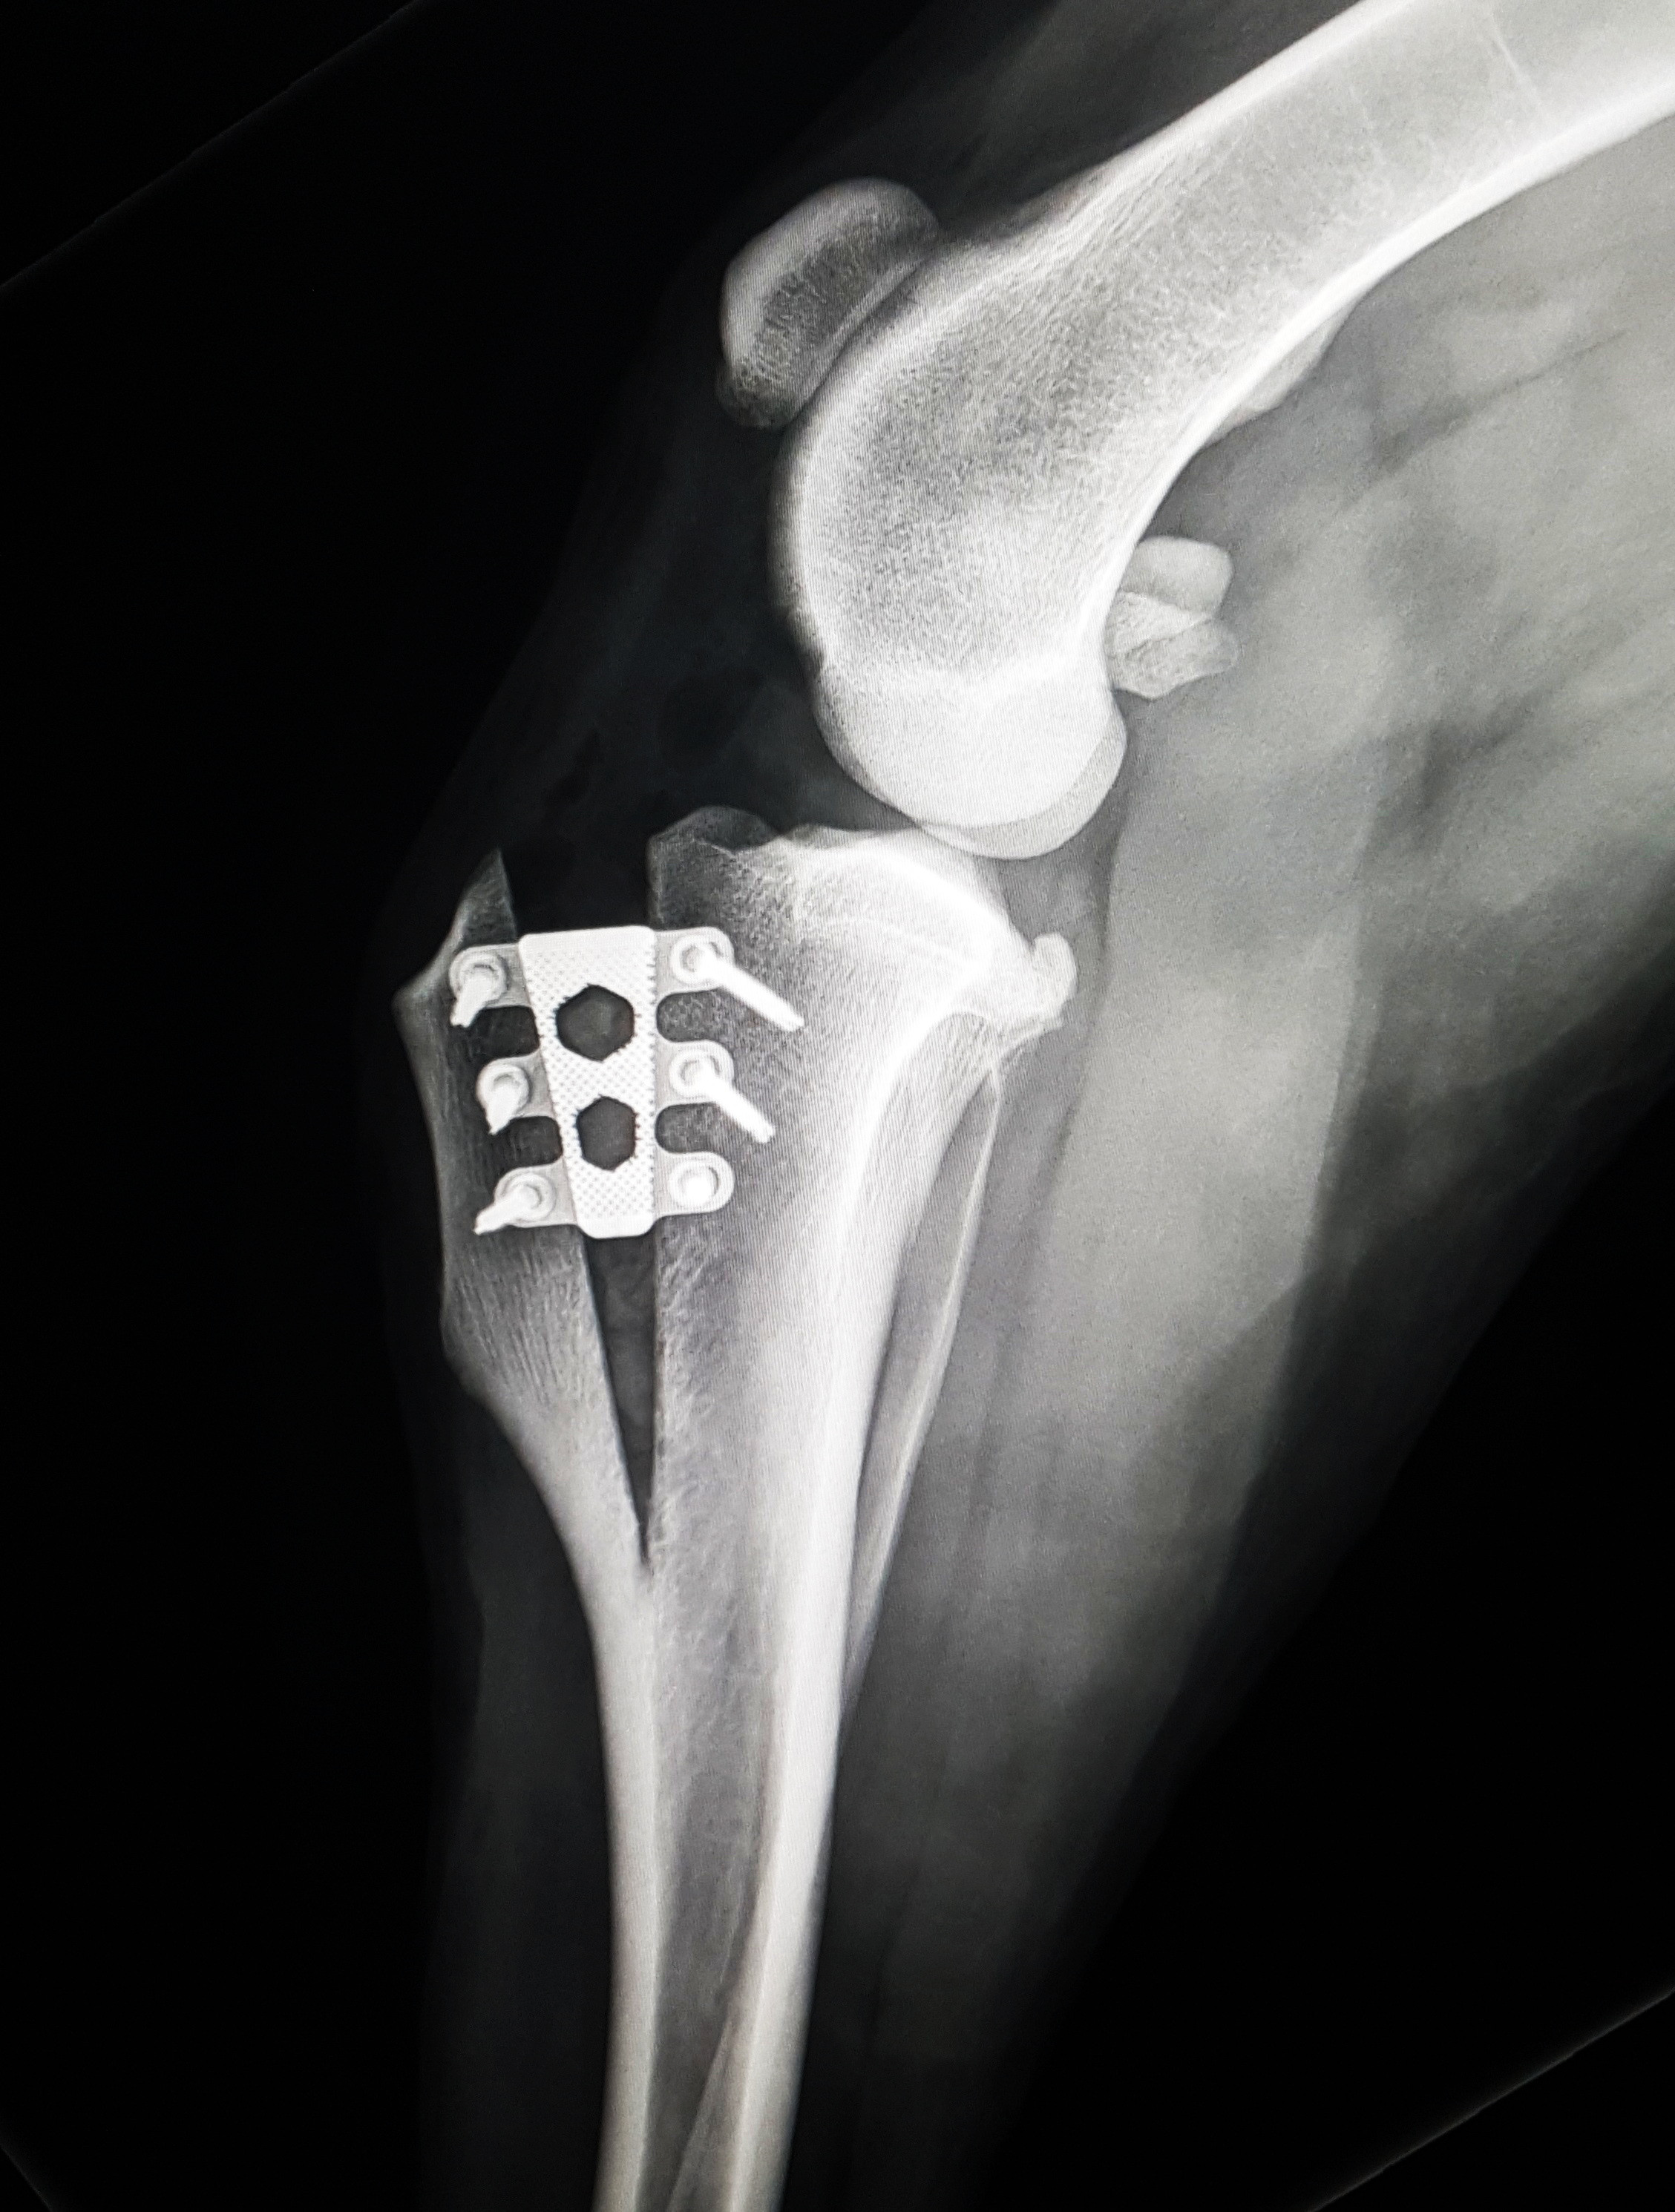

This one-day practical course focuses on the TTA Rapid procedure for cruciate repair, including techniques for addressing patella luxation concurrently.

Geared towards veterinarians interested in mastering the TTA Rapid technique, this practical course includes sawbones and wet lab sessions for hands-on learning. Participants will discuss diagnosing cruciate ruptures, preoperative planning, surgical guidelines, and potential complications and solutions. The course will also explore unique methods for treating patella luxation simultaneously, providing ample opportunities for questions and hands-on practice.

- Refresher of stifle anatomy and diagnosis cruciate rupture

- Pre operative planning for TTAR procedure

- Treating Patella Luxation in conjunction with cruciate surgery